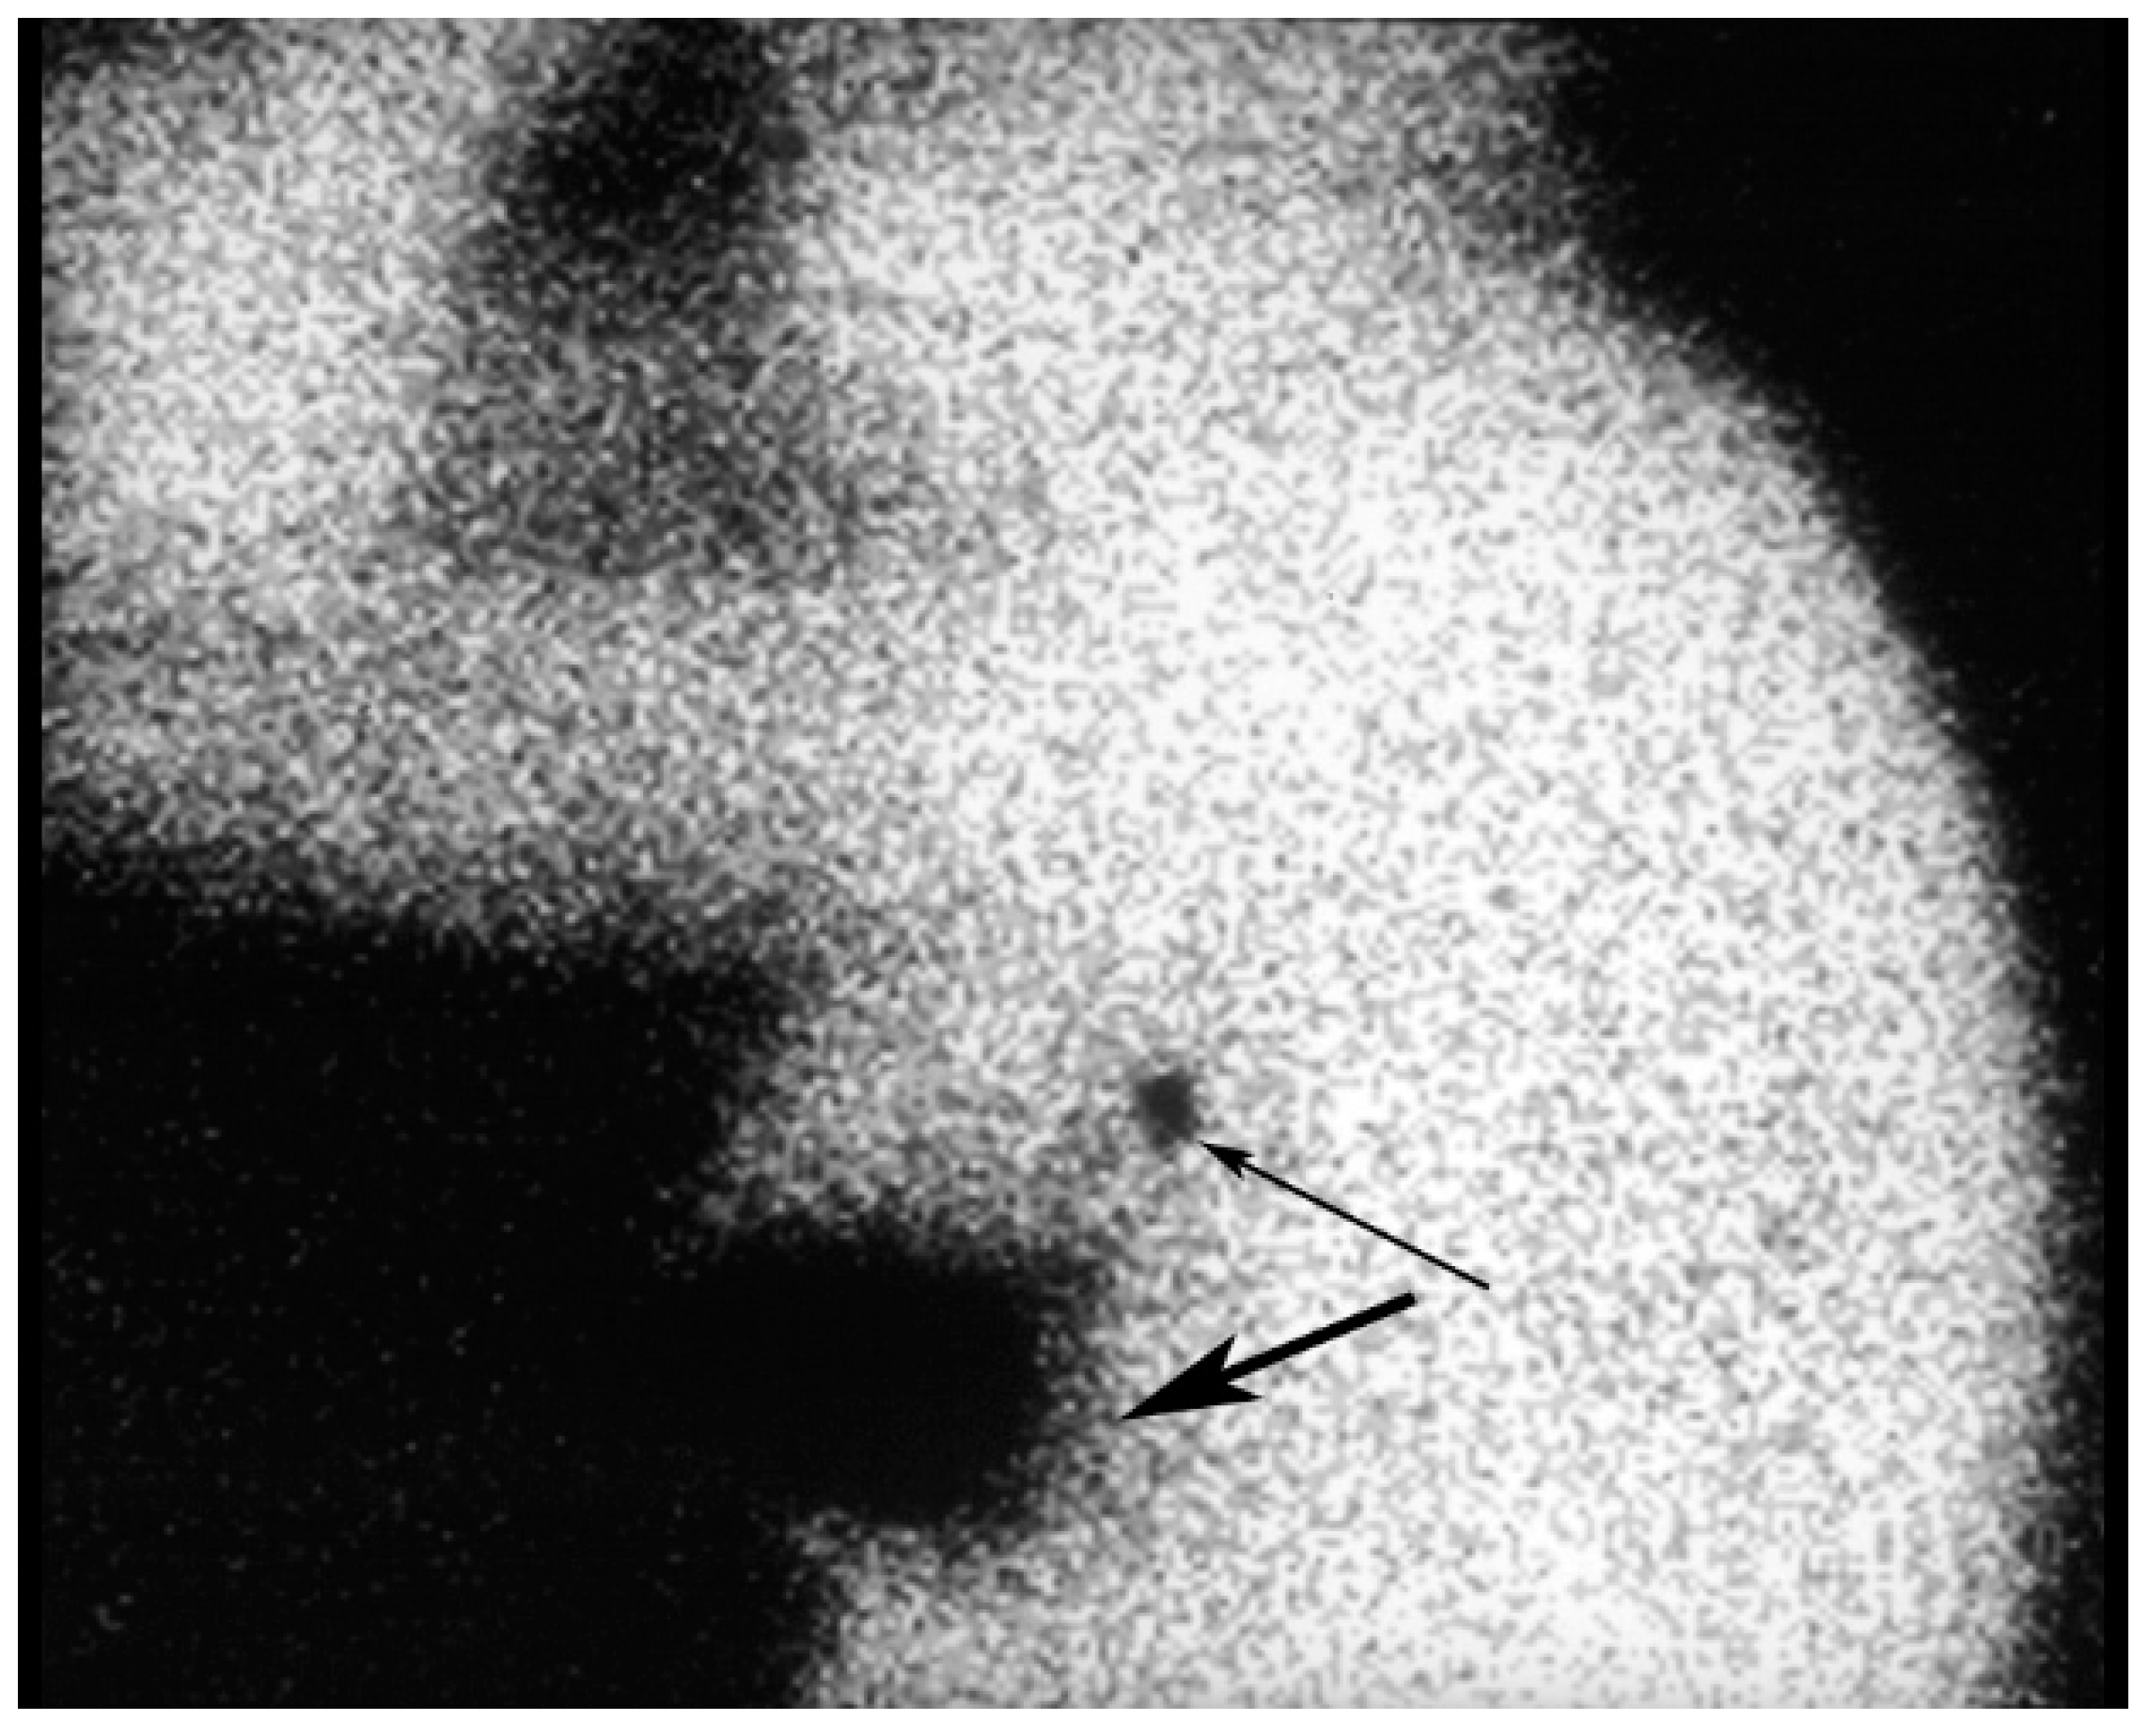

8. Lymphoscintigraphy

Figure 12. An injection site in the upper outer quadrant of the right breast (large arrow) is seen adjacent to a low axillary SLN (small arrow).